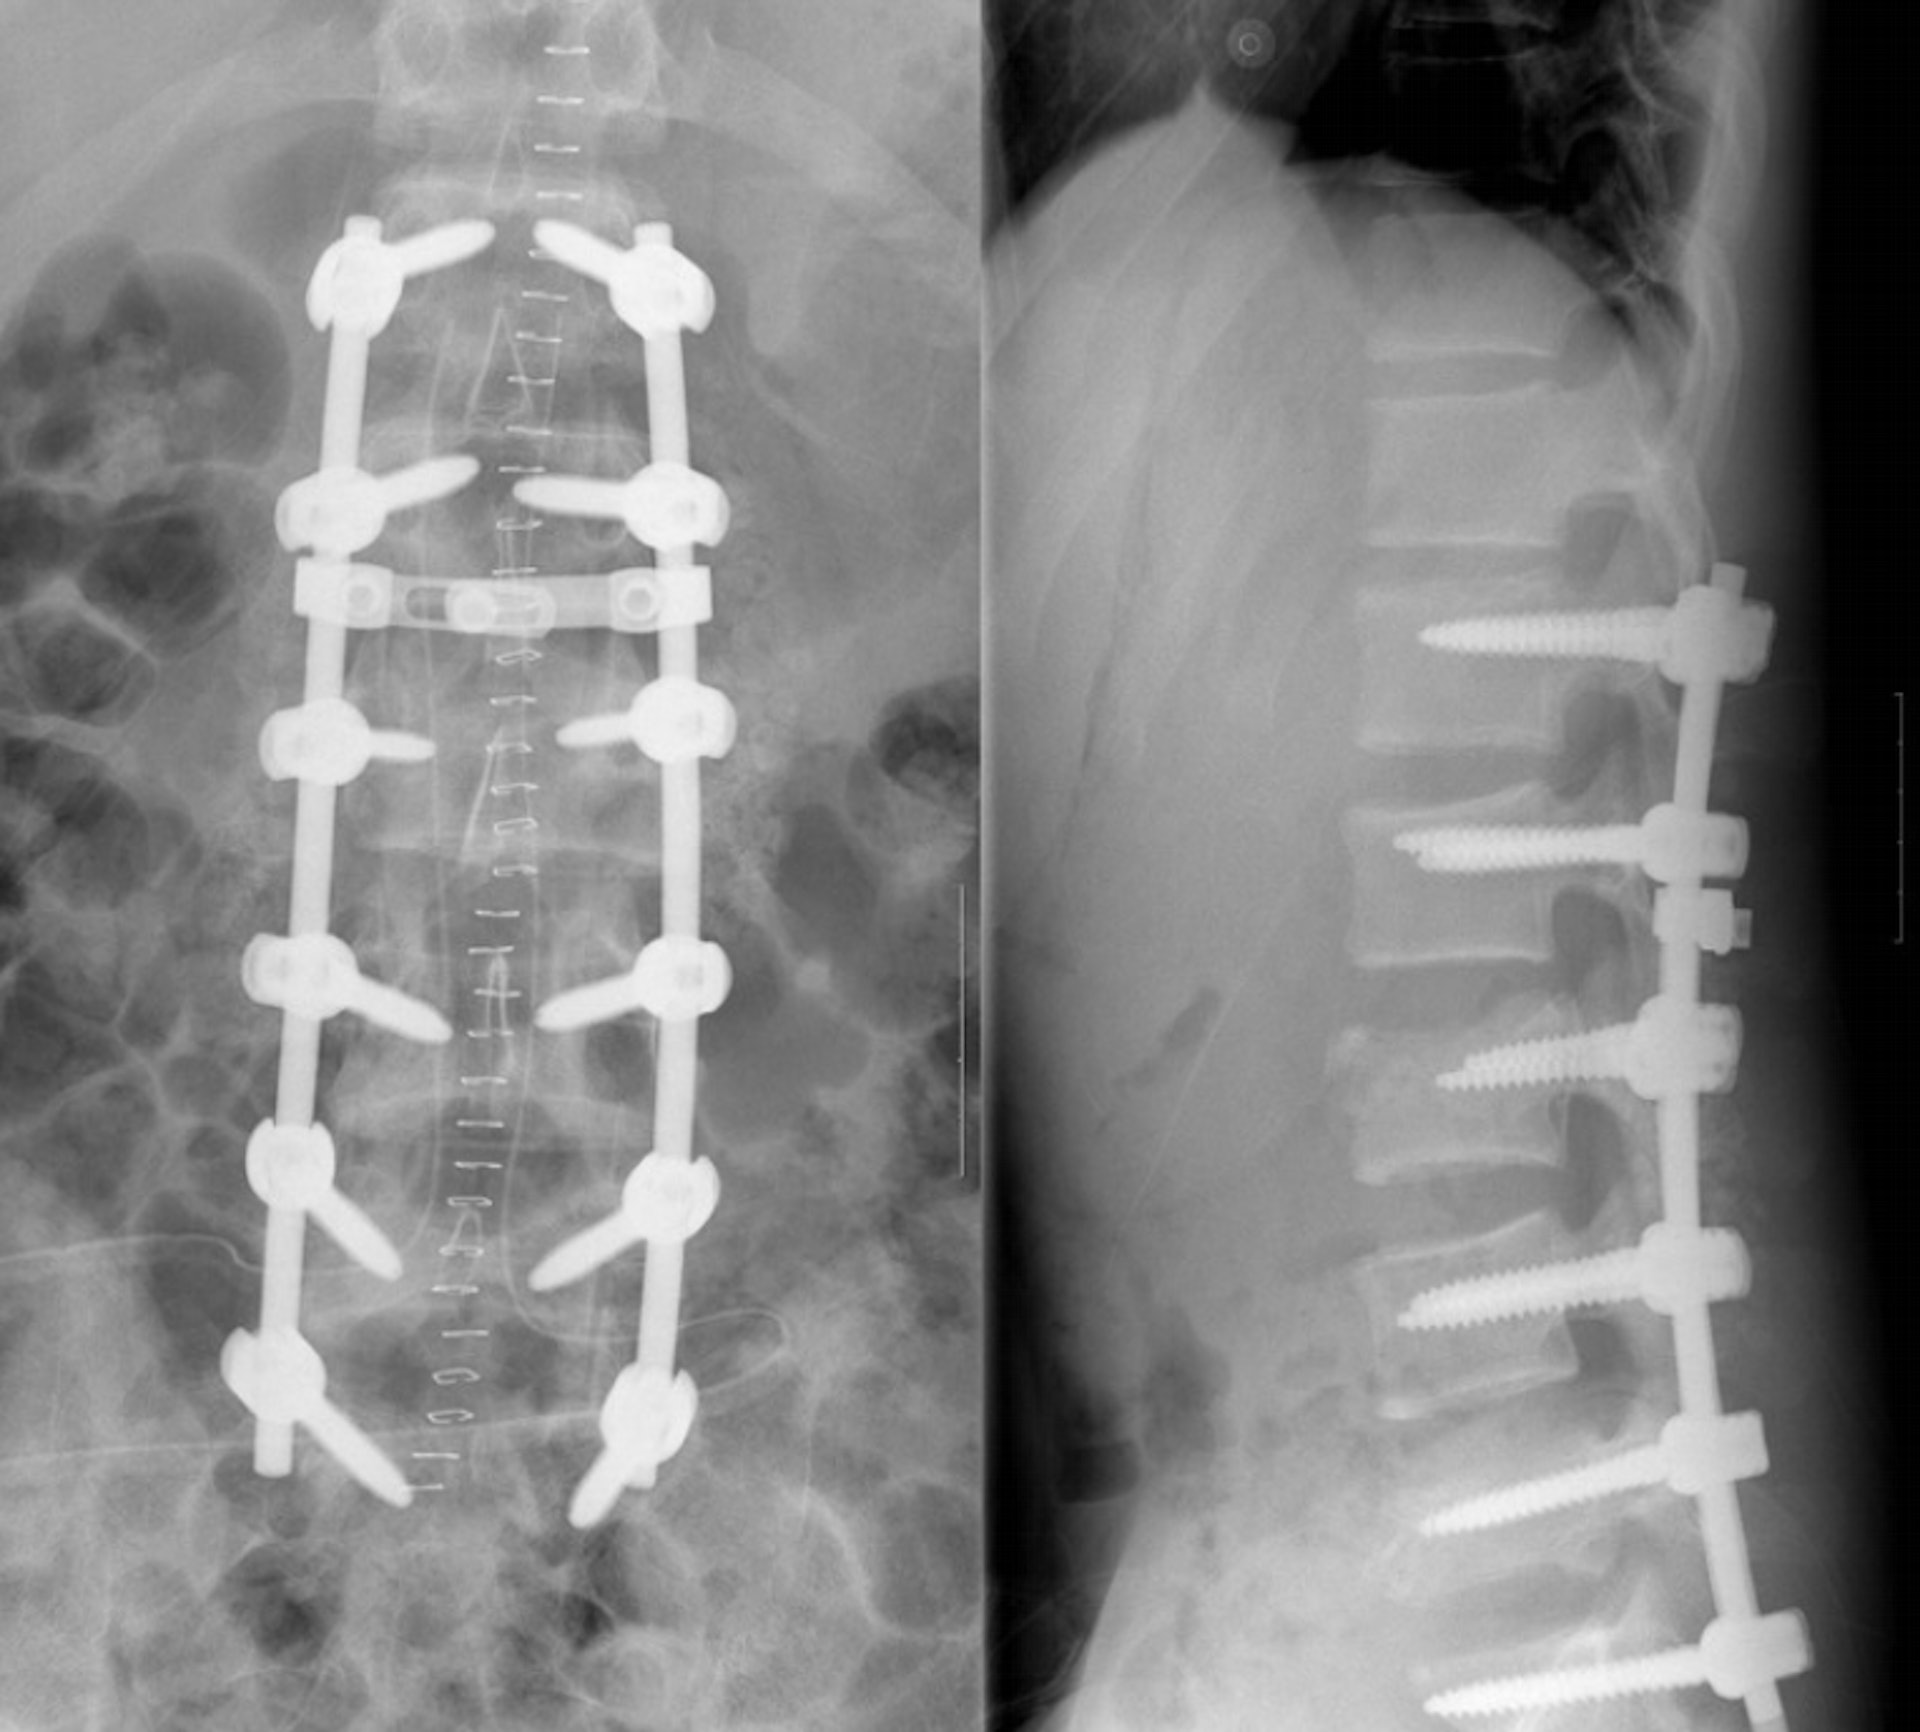

2015年9月18日过后,在班内遭受欺凌9个月而轻生的金始元做了两次背部支架手术,又在精神病院住了一个月。时至今日,他不认为当年的霸凌事件得到妥善解决,创伤不只留于他的背上,也在心里。

金始元(化名)在班内遭受欺凌9个月而轻生的金始元做了两次背部支架手术。